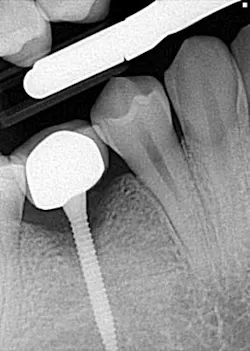

Hygiene. It can be agreed upon that if an implant can’t be kept clean, then the potential for failure and difficulties rise exponentially. A 90-degree angle between the implant and crown is virtually impossible to keep clean and maintain. As amazing as some hygienists are, it is impractical to expect that a curette can get into that space to clean it without making hamburger of the tissue. The implants were cemented on, so they are not easily retrievable. The emergence profile is nonexistent. Do natural teeth look like this? I would submit that when restoring implants, it is our job to mimic the shape and emergence profile of natural teeth as closely as possible. When we don’t, then we lose the inherent cooperation and benefits that the tissue can provide. To help the parents understand this concern, I showed them an example of a traditional implant vs. the “pumpkin on a toothpick” implant. The side-by-side comparison spoke for itself.

vs.

Longevity and function. Premolars don’t get the brunt of mastication forces, but they definitely get their fair share. If the occlusal forces are not centered over the implant just right, then we observe a first-class type of lever that can cause long-term stability issues. It could be argued by some that the 20 mm implant length could render a certain amount of support, but again, the aforementioned point must be referenced — there is/was adequate space for wider based platform implants to be placed.